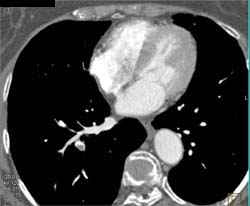

Pulmonary Embolism